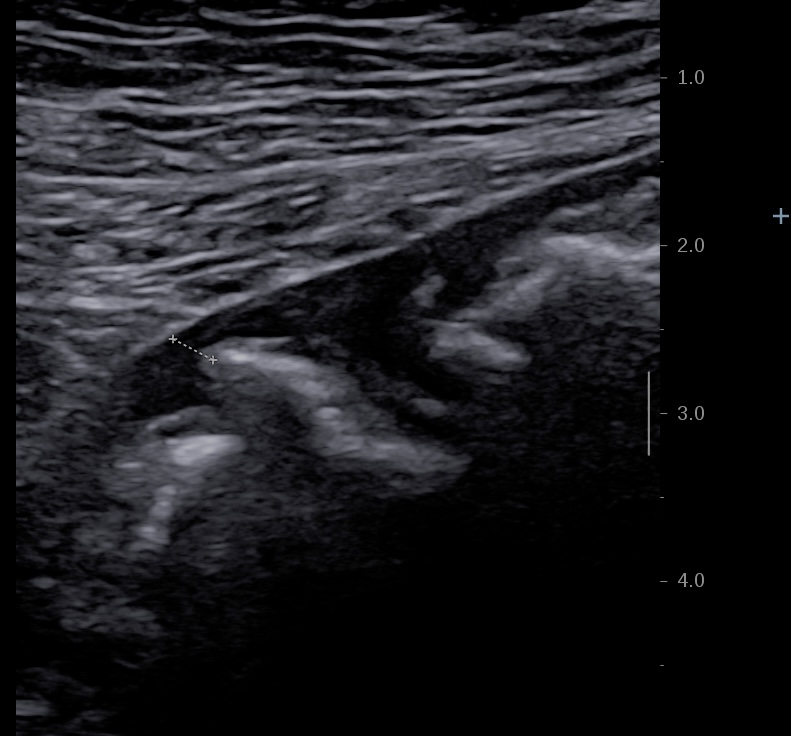

C'est plutôt un diagnostic différentiel des MICI car on l'observe surtout au niveau du sigmoide dans la maladie diverticulaire.

En basse fréquence la musculeuse épaissie hypoéchogène souligne les parois du sigmoide

Epaississement musculeuse et image diverticulaire

Musculeuse sigmoidienne épaissie paroi non inflammée